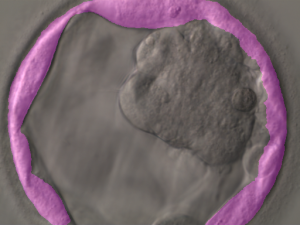

The system is powered by AI models that perform classification, detection and segmentation on the images. Segmentation of blastocoel cavity, trophectoderm and ICM computation on day 5 images is conducted. Thereafter, IVF embryo gradings are performed that are based on Istanbul concensus. All the images are stored in a central repository for AI model training.

KritiLife platform will grade the embryos on the basis of their development and respective images captured on day 5 as per pre-defined criteria. This aids embryologists in gaining a second opinion to select embryos that possess the best potential for viable implantation.